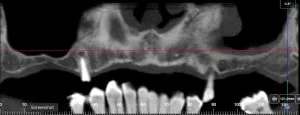

An alternative method of tooth replacement is to insert implants into the jawbone to support the false tooth or teeth. Such implants may become firmly attached or integrated with the bone and act in a similar manner to a tooth root. If an implant is placed immediately or soon after a tooth is extracted, jawbone is preserved and its further loss prevented. For this reason, it is best not to delay the decision to place implants, as bone will be lost with time which can make the placement of implants more difficult. However, even after considerable bone loss has occurred, it may still be possible to place an implant although additional bone grafting techniques may be required.